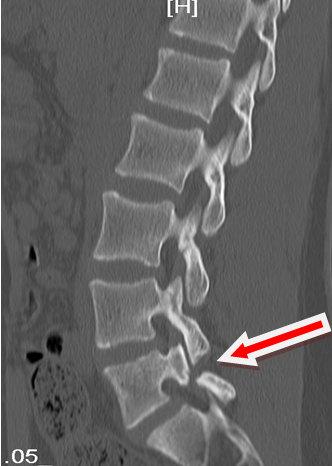

影像学(CT)检查资料:

影像学资料解读:影像学检查可见L5/S1双侧椎弓峡部裂并椎体I°滑脱,椎间盘无退变。

确诊:腰椎峡部裂